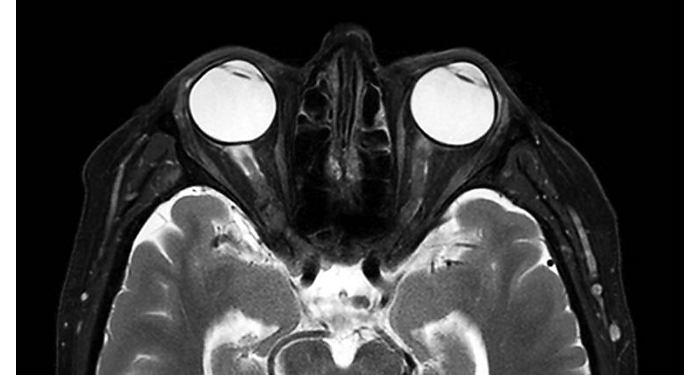

Imágenes de la IRM de campos oscuros de un paciente con VIH con vasculitis cerebral

Las imágenes de campos oscuros ayudaron a sugerir el diagnóstico y elegir el tratamiento.